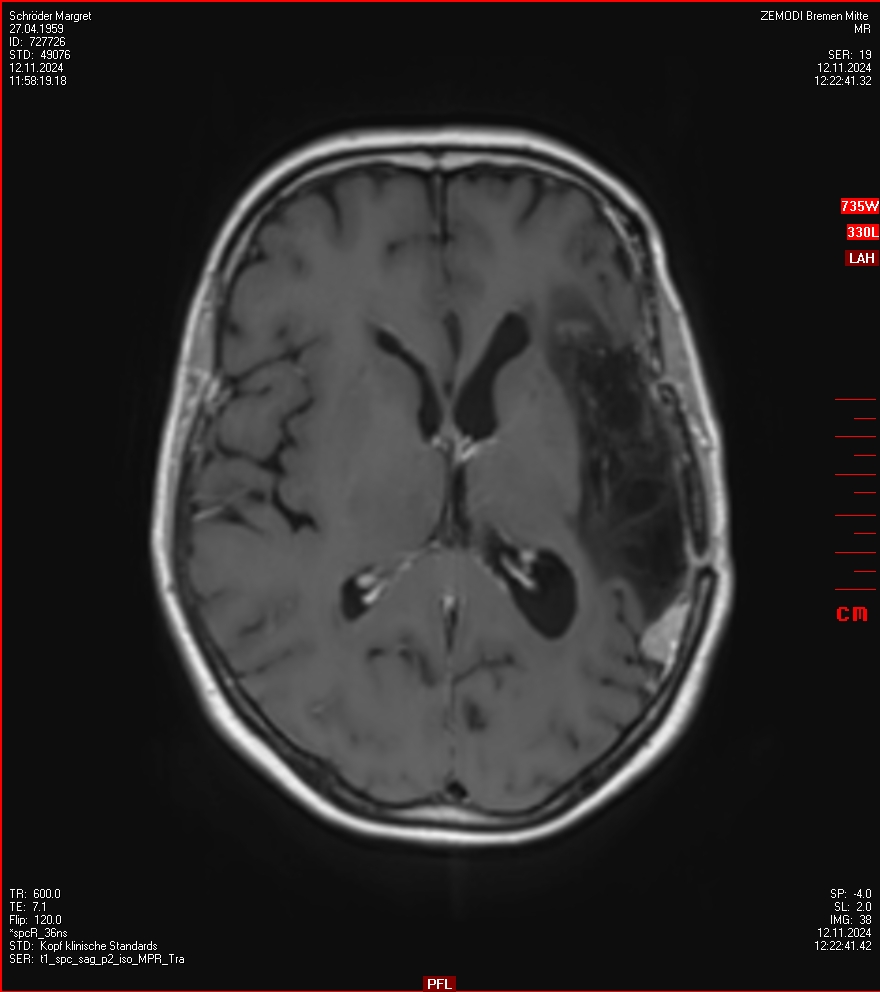

MRT vom 12. November 2024

So nun ein paar neue Bilder aus meinem Kopf. (Durch klicken bekommt man eine größe Ansicht eines Einzelbildes).

Die letzten drei Bilder Zeigen aus meiner Sicht den Tumor, der im Jahr 2021 bestrahlt wurde.